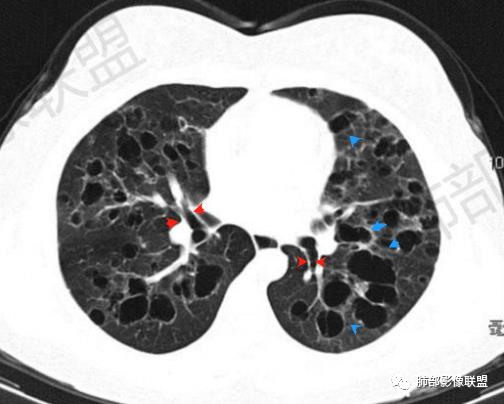

晨读:双肺多发大小不等囊腔影,部分囊有融合,形态不规则,部分壁偏薄,部分囊壁偏厚,囊壁可见结节?血管?右肺上叶及左肺下叶可见条状高密度影,双侧胸膜结节样增厚,临床年轻女性,考虑LAM,鉴别LIP

晨读:女,31,间断咳嗽咳痰9个月,双肺多发大小不等囊泡影,壁薄厚不均,部分囊泡融合成片,双肺另见结节影,边界清晰,考虑PLCH,LAM。

晨读,青年女性,双肺及胸膜下多发大小不等囊腔,大部分呈薄壁,部分囊壁略厚,边缘毛糙,部分囊腔有融合,双肺内散在条状高密度影,考虑LAM

影像:双肺散在囊性病变,不规则,壁厚,部分见结节

晨读:女,31,间断咳嗽、咳痰9月。卵巢交界性囊腺瘤术后。胸部CT:双肺多发大小不等薄壁囊腔影,部分融合,形态不规则,个别囊壁偏厚。右肺上叶及左肺下叶纤维索条影。左下叶不规则囊腔影,壁不均匀增厚,周围不规则实性成分加GGO,放射性毛刺,胸膜牵拉。考虑:囊腔型Ca?转移?鉴别PLCH,Lam,LIp,BHD,CF,CPAM等,听大咖解析。

胸部CT:两肺多发囊腔,中上肺受累为主,囊腔形态不规则(囊有点丑),分叶状,囊壁厚薄不均,大部分囊壁薄。尚有一些结节影。